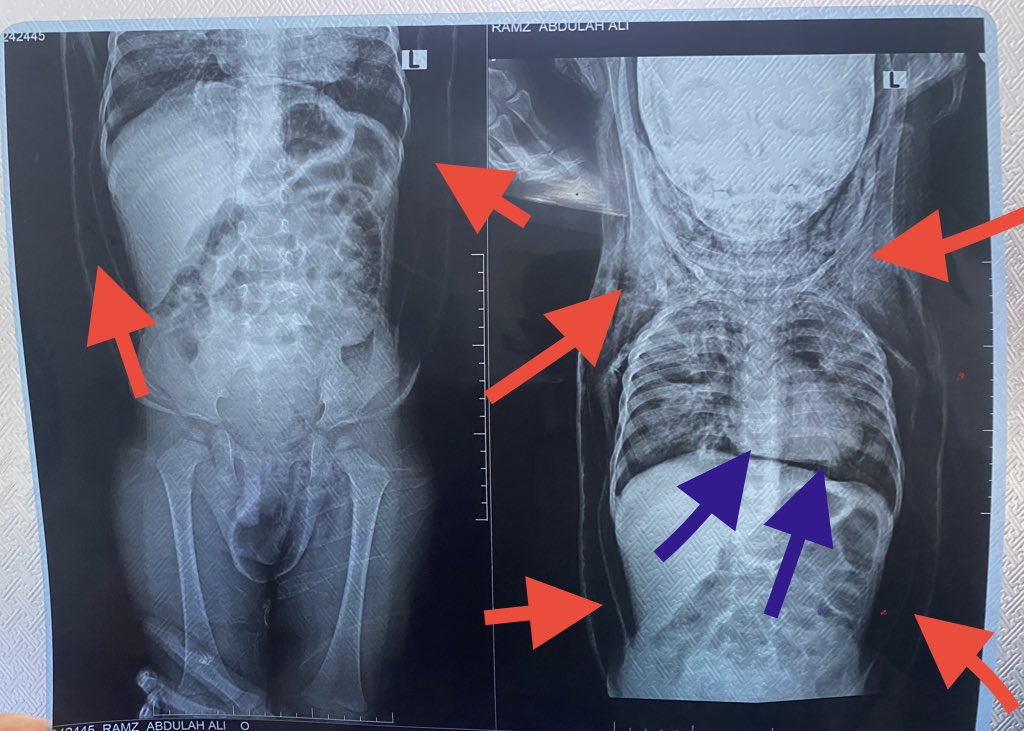

A 2-y-o male pt with a Hx of hospitalization for pneumonia suddenly presents with generalized body swelling and severe respiratory distress.There is no Hx of trauma.On PE,crepitus is noted when the swollen areas are palpated.

Patient with history of generalized body swelling and subcutaneous crepitu suspected emphysema,

the #imaging_findings show:

• Severe pneumomediastinum(green arrows) assoicated with severe chest wall emphysema extend to the neck and down to the abdomen (red arrows)

with patchy area of consolidation and ground glass attenuation affecting the right upper lung lobe , right lower lung lobe, left upper lobe

#Diagnosis:

-The above-mentioned

findings keeping with severe

#pneumomediastinum,diffuse

#soft_tissue_emphysema of the neck, chest and abdomen.Patchy area of consolidation of both lungs (likely infection Or contusion).